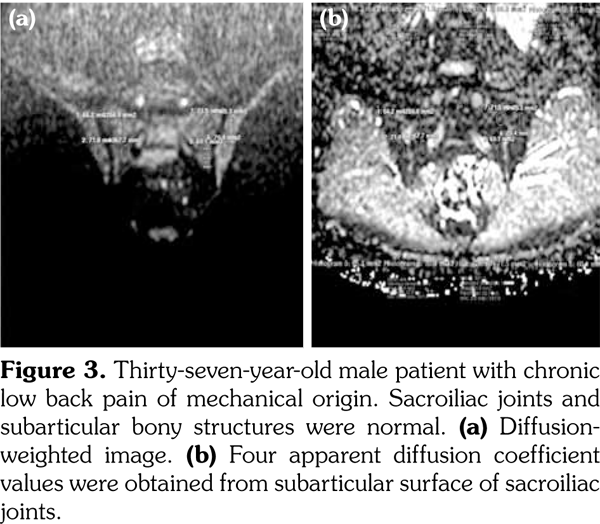

Sacroiliac joints were assessed according to ankylosing spondylitis criteria. Before evaluation of standard MRI protocol, patients’ information was removed from images. Afterwards, two experienced radiologists evaluated the images for the presence of inflammatory activity twice at separate sessions to assess interobserver variability. Following the examination of T2-weighted SPIR, contrast- enhanced T1-weighted SPIR, and DWIs at b values of 600 s/mm2, two radiologists and rheumatologists reached a consensus on the disease activity in the light of positive features of Berlin criteria. The DWIs were transferred to a separate workstation (Phillips, Extended MR workspace, 2.6.3.2.HF3, Netherlands). ADC maps were generated. T2-weighted SPIR images, contrast-enhanced images and diffusion-weighted images with ADC maps were put on the screen side by side. In the disease group, the hyperintense lesions on T2-weighted SPIR images and enhanced focuses on contrast- enhanced images were noted and the same lesions were marked on DWI images and ADC map. A circular ROI with a range of 40-75 mm2 was placed in those areas. In the control group a circular ROI was placed in the subarticular area of joints. Also, the same process was performed for the normal-appearing bone marrow areas near the joints of the disease group (Figure 2). Four standard measurements were conducted from each joint, including two on sacral and the other two on the iliac side for all patients (Figure 3). Additionally, two measurements were conducted from the fifth lumbar vertebra and one from each iliac wing (Figure 4). All measurements were performed twice. ADC values were expressed as square millimeters per second. The r-ADC ratio was calculated by dividing ADC value of subchondral bone or inflammatory lesions to ADC values of the fifth lumbar vertebra and iliac wings.